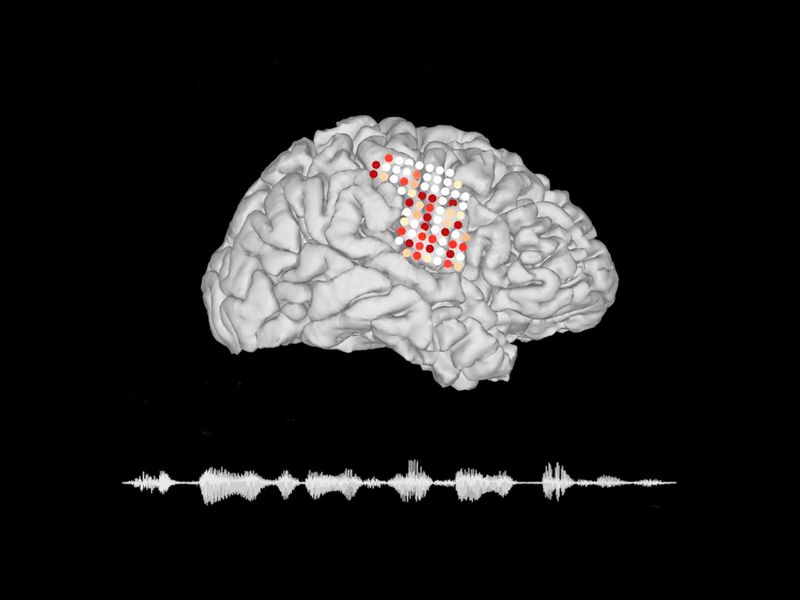

عملکرد این تکنولزی جدید به این صورت است که الکترودهایی بر مغز قرار می گیرند و سیگنال های مغز را دریافت می کنند و در نهایت این سیگنال ها رمزنگاری خواهند شد و به گفتار تبدیل می شود. به طور شبیه سازی کاملی از روند تبدیل سیگنل های مغزی به گفتار طراحی شده که ظاهرا از عملکرد بالایی هم برخوردار بوده است. البته این تکنولوژی هنوز با مشکلاتی روبرو است اما می تواند بر اساس روند مغز گفتار قابل فهم و واضحی را ارائه دهد.